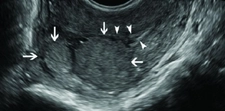

Böbrekte kistik lezyon, genellikle böbrek dokusunda sıvı dolu kesecikler (kistler) oluşturan, benign (iyi huylu) ya da malign (kötü huylu) olabilen yapılar olarak tanımlanabilir. Bu lezyonlar, böbreklerin normal işlevlerini etkileyebilir ve bazı durumlarda belirti vermeden uzun süre varlık gösterebilirler. Kistik lezyonlar, genellikle görüntüleme yöntemleriyle (ultrason, bilgisayarlı tomografi, manyetik rezonans görüntüleme) tespit edilir. Kistik Lezyonların TürleriBöbreklerdeki kistik lezyonlar, birkaç farklı türde sınıflandırılabilir:

Tanı ve Teşhis YöntemleriKistik lezyonların tanısı, çeşitli görüntüleme yöntemleri ile konulmaktadır: